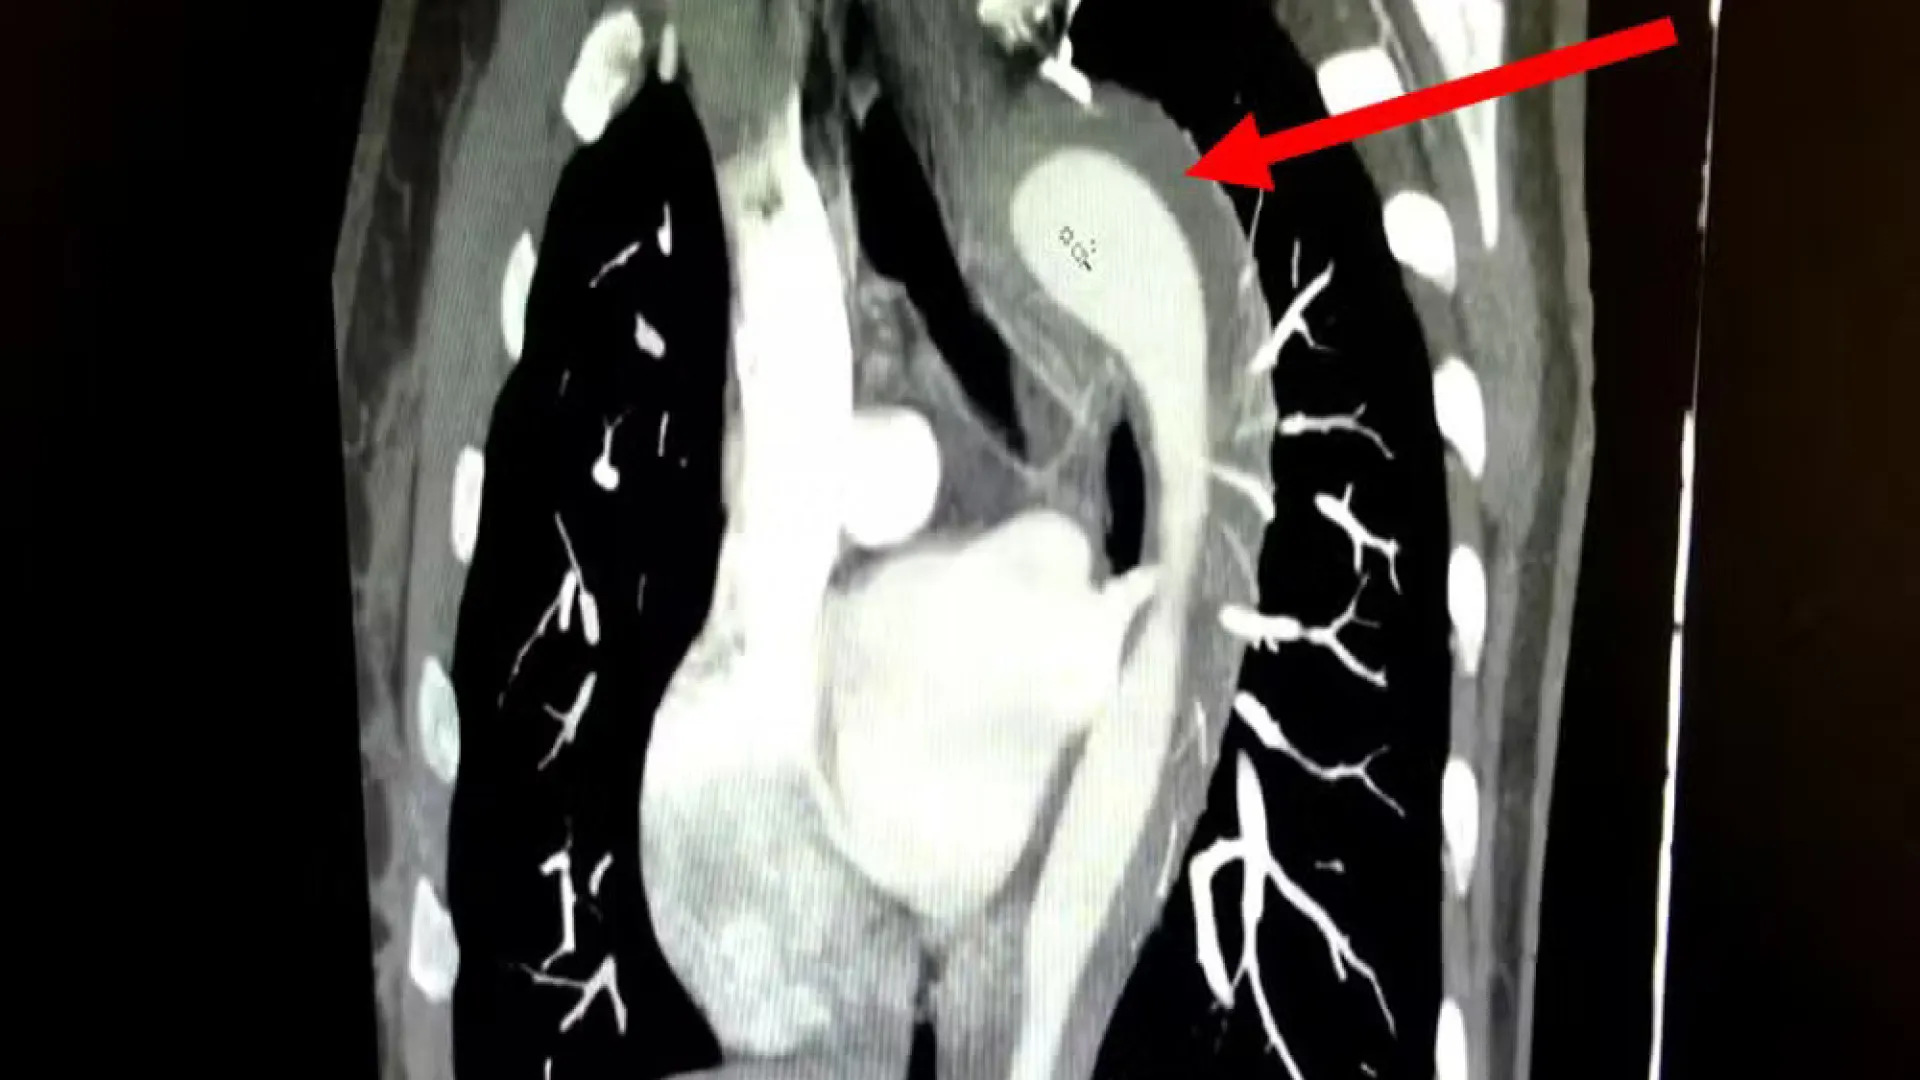

Um caso raro e de alto risco envolvendo a ruptura da aorta foi relatado pelo American Journal of Case Reports. A paciente, uma mulher de 45 anos, d…